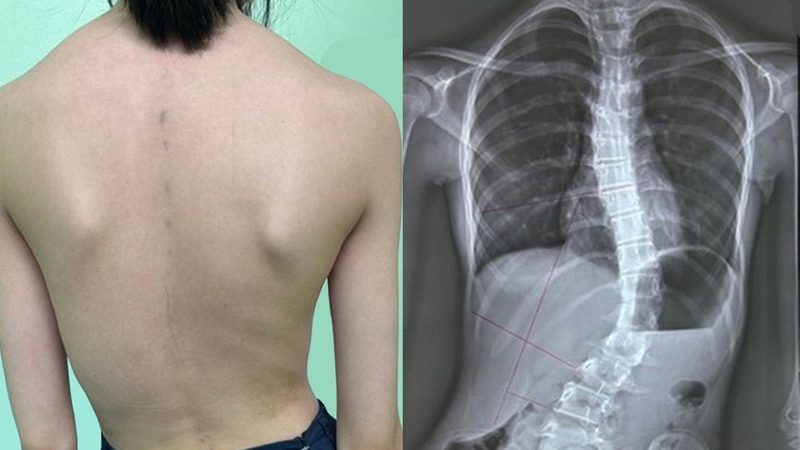

Vẹo cột sống tự phát hay còn gọi là vẹo cột sống vô căn thường gặp ở trẻ em khoảng 8 - 10 tuổi và khởi phát nhanh khi trẻ đến tuổi dậy thì. Tình trạng này sẽ khiến người bệnh bị gù, đau thắt lưng và gây ra nhiều ảnh hưởng đến sinh hoạt thường ngày.

Cong vẹo cột sống là tình trạng cột sống bị cong bất thường đổ về phía trước, phía sau hay bị lệch sang một bên. Vẹo cột sống có nhiều nguyên nhân như bẩm sinh, do di truyền, vẹo sau khi phẫu thuật, do hệ thần kinh có vấn đề,…

Vẹo cột sống tự phát không rõ nguyên nhân, là dạng thường gặp nhất của bệnh lý vẹo cột sống. Theo thống kê có đến 80% ca bệnh vẹo cột sống là vô căn, tỷ lệ mắc phải chủ yếu là trẻ em, thanh thiếu niên trong độ tuổi dậy thì. Vẹo cột sống tự phát chưa xác định được chính xác nguyên nhân gây bệnh. Một số nghiên cứu cho rằng căn bệnh này có nguyên nhân do di truyền nhưng các yếu tố khác như nội tiết tố vẫn có thể liên quan đến nguyên nhân gây bệnh. Trên thực tế hiện nay có khoảng 30% người bệnh vẹo cột sống vô căn có tiền sử gia đình.

Vẹo cột sống tự phát chữ S còn được gọi là vẹo cột sống kép, có liên quan đến cả phần đường cong ngực và đường cong thắt lưng. Tình trạng cột sống cong chữ S rất khó phát hiện ở thời điểm mới khởi phát vì đường cong đôi khi có xu hướng cân bằng lẫn nhau.

Vẹo xương sống chữ C là khi đường cong cột sống đi theo một hướng và tạo thành hình chữ C. Loại cong vẹo hình chữ C ít nguy hiểm hơn chữ S. Tuy nhiên nếu tình trạng này không được điều trị sớm thì sẽ có nguy cơ chuyển từ chữ C sang cong vẹo chữ S.